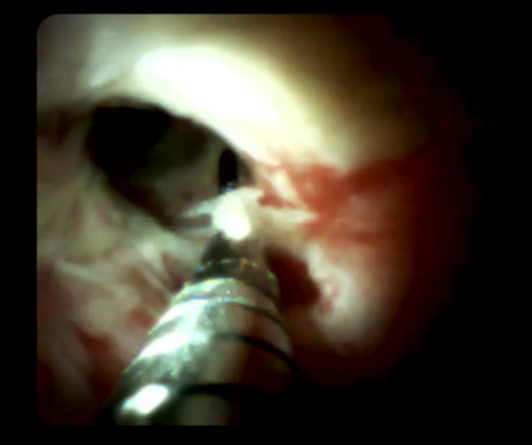

另外,經(jīng)口膽道子鏡光纖直視系統(tǒng)(SPYGLASS)是一種電子膽道子鏡,可通過十二指腸鏡到達(dá)膽管或胰管內(nèi),對病變進(jìn)行直視觀察,高清高分辨率顯示病變、并精準(zhǔn)指導(dǎo)活檢,對于膽胰管狹窄的診斷治療具有重要意義。

5466bc1aa2b44eeabb2f6ab4904c0f6c.Png  0c9bb25f31ed492197b787eecbde3974.Png

經(jīng)口膽道鏡下膽總管碎石